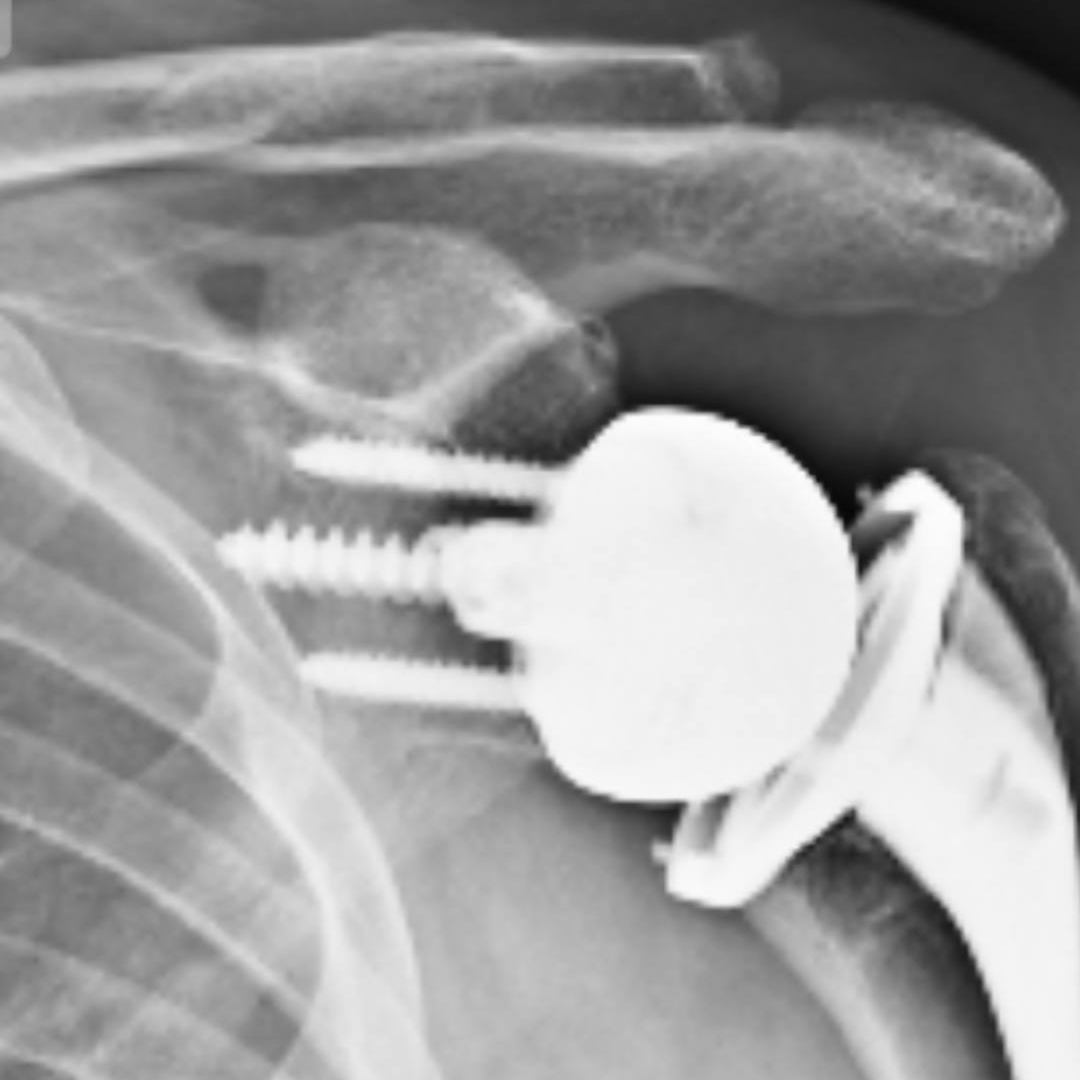

- 수술 치료

- 금속 핀, 플레이트, 나사 고정

- 골절이 심하거나 어긋난 경우

- 기능 회복을 위해 정렬이 중요한 경우